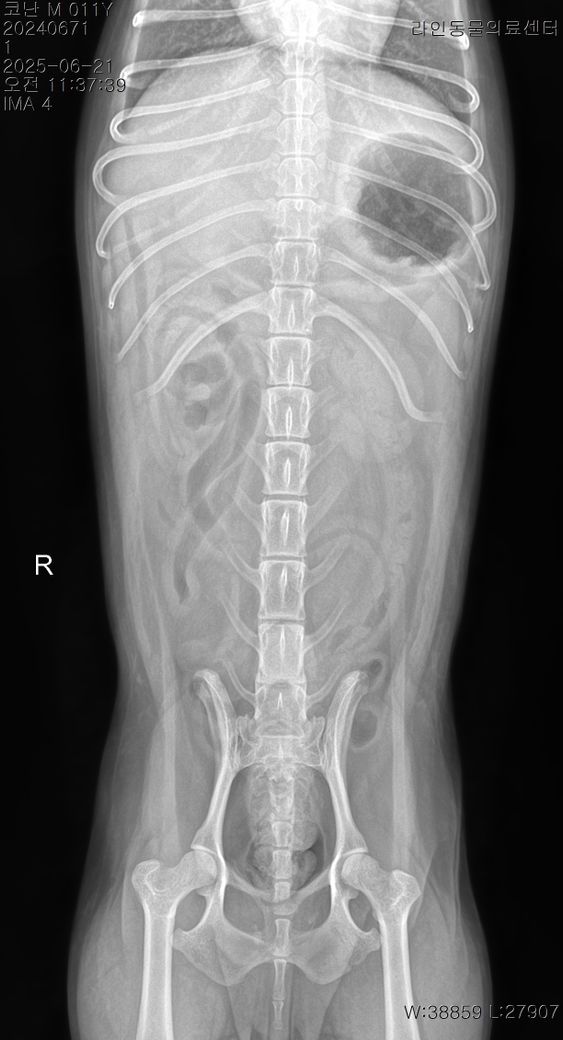

밤에는 멀쩡하다가 오늘 아침부터 애가 갑자기 강아지 혀가 파래지고 복부가 돌처럼 엄청 단단해지고 똥을 싸고 (정상변 5덩어리) 과호흡이 온 경우는 무슨 경우인가요? 애가 안절부절못하면서 집안을 돌아다니면서 혀를내밀고 헥헥거리며 그래서 24시 응급으로 동물병원에선 피검사는 안하고 그냥 엑스레이만 찍었는데 장염이 있다고 하는거같고 변이

안에 있다하는데 별다른 처치를 안하고 돌려보내길래 집에 와서보니 애가 멍해지고 밥을 현재 오후 1시간 이 다되가는데 한끼도 안먹었고 그저 낑낑만 거리고 앉아만있는데 대체 이유가 무엇일까요? 폐는 괜찮다하고 심장병이 있긴한데 심잡음도 별로 안들린다고 그냥 돌려보냈는데 배는 다시 물렁해졌고 헥헥 거림도 신기하게 없어졌고 혀만 약간 보라색빛이 납니다 뭘해야할지도 모르겠고 이게 맞는지도 모르겠습니다

특이사항은 애가 췌장염도 있고 심장병도 있고 장도 안좋고 위에 가스가 찼다고 합니다

그리고 원래 아침부터 밥달라던애가 희한하게 요즘 11시가 되도록 밥을 안찾고 억지로 먹는 그런 느낌도 있고 또 저녁에는 밥을 계속 미친듯이 달라고 또 달라고 짖습니다 그리고 복명음이 들린지 거의 6개월은 넘은거같은데 복명음이 심하게 들립니다 포피염도 있고 노란 고름이 나오며 애가 어느순간부터 실외배변을 고집하고.. 변이나 오줌을 참는 습관이있고 애가 소화력이 약해졌는지 애가 배가 단단해지면 산책을 10분 정도 시켜주면 배가 다시 물렁해집니다 헌재는 허리디스크 때문에 가바펜틴과 엔세이드 근이완제를 먹이고 있고 허리디스크 때문에 산책은 전혀 안해주고 있으며 엑스레이상 가스와 변이 있는 상태인데(아침에 5덩어리의 변을 누었음에도) 왜 이렇게 소화기가 문제인지를 도무지 이유를 모르겠습니다 11살 토이푸들입니다 그리고 식이알러지 증상도 있습니다 (한쪽 턱을 긁는다던지, 귀를 긁는다던지 발을 빤다던지 하는 증상) 마지막으로 애가 밤만되면 꼭 이불을 이유없이 하루 종일 빨아서 이불이 항상 침으로 범벅이 되있습니다 (이것도 거의 근 반년은 된거같습니다) 어제 밤은 입맛을 살짝 쩝쩝 다셨으나 별 다른 증상은 없었습니다 병원에 가도 하는건 없고 그냥 산소방에 넣어두고 엑스레이찍고 청진하고 이게 다인제 이게 맞는 처치인지도 모르겠고 약 하나 주사하나 뭐 하나 조치가 취해진게 아무것도 없는 상황입니다 제발 예측이 되는 질병들이 있으면 알려주세요 심잡음은 약하게 들린다하여 b1 같다고 합니다 그리고 포피에는 노란 농이 나오고 있고 만지려고 하면 엄청 신경질적으로 변하는데 이 경우 장도 저렇게 안좋은데 포피염 항생제를 처방받아야할지 이것도 감도 안옵니다.